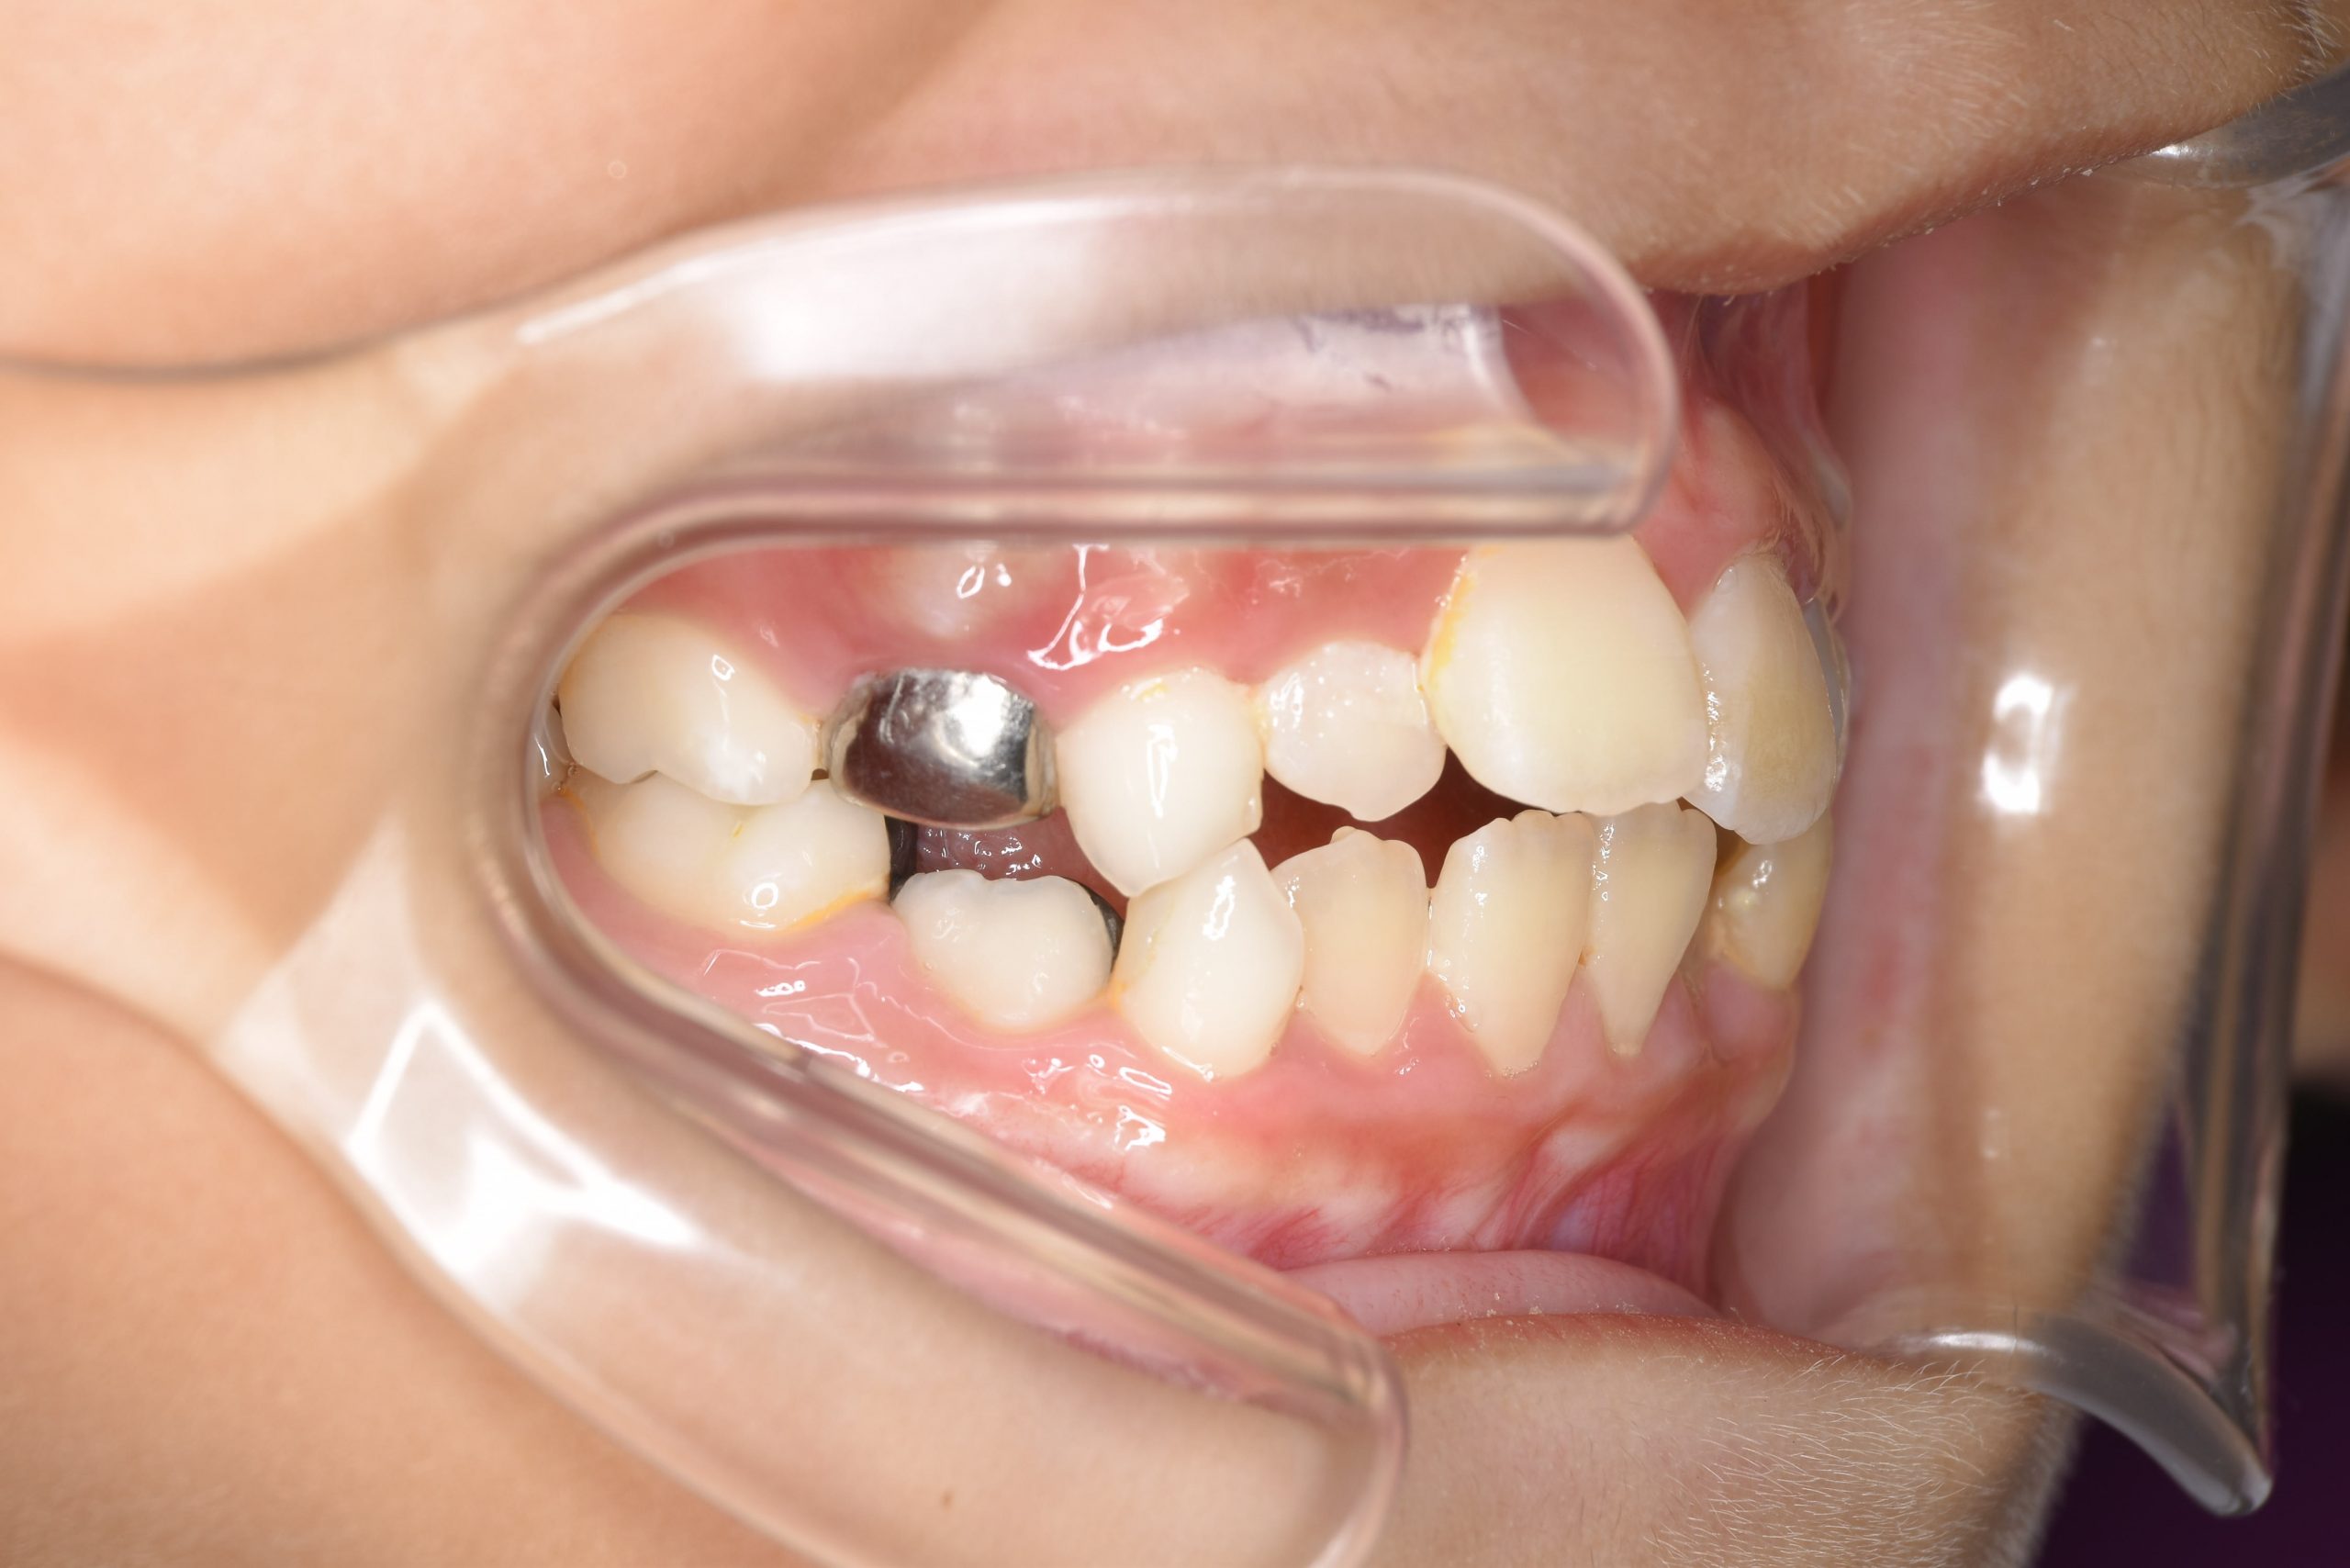

ビフォー

子どもの矯正治療|症例_169

主訴 歯並び|嚙み合わせ|口呼吸

施術内容 上顎急速拡大装置と下顎リンガルアーチを用いて上下顎骨を拡大した。

その後マウスピース型矯正装置で歯牙を配列し良好な咬合を獲得した。